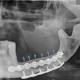

Padova, Mandibola artificiale impiantata con successo: prima volta in Italia

Mandibola artificiale – Ancora una volta la medicina Italiana protagonista assoluta con eccellenti risultati.Per la prima volta nel nostro paese, a Padova, è stato eseguito un trapianto artificiale di mandibola, il volto di un paziente italiano di ...